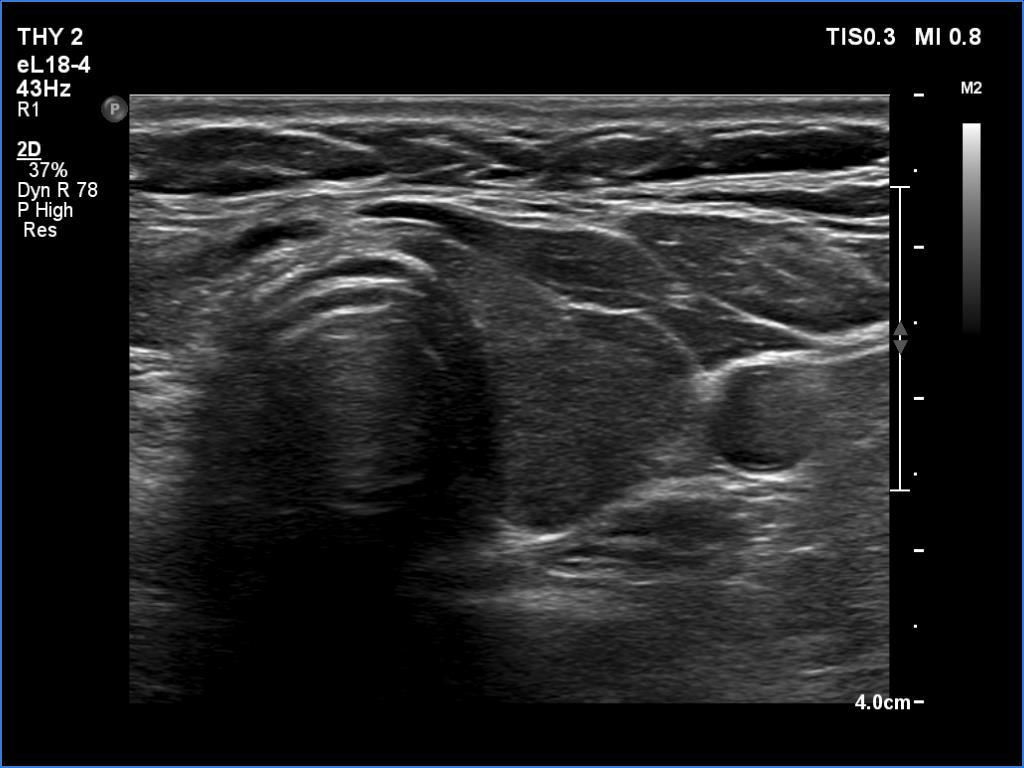

Five years after the surgery (second row of images):

Ultrasonography. The right lobe was replaced by connective tissue. The left lobe was composed of two hypoechoic parts divided by connective tissue. Compared with the previous examination, the left lobe has increased in size.

After the surgery, the left lobe became larger. A connective tissue hedge divided the lobe into two parts. It is to be avoided to misinterpret these areas as pathological nodules.